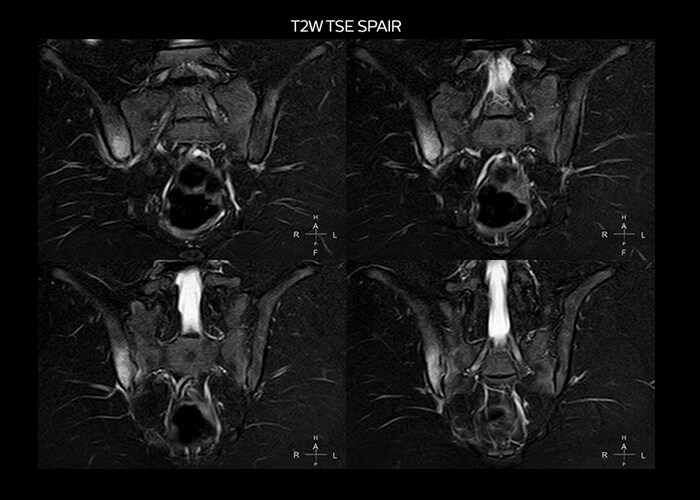

“On average, we scan about 80 patients per day, but on some days we scan well over 100 patients. The scanner is in use 7 days per week, operated 20 hours per day on week days and 8 hours per day in the weekend,” Mr. Tuna says. “To avoid coil changes we plan examinations of similar anatomies back to back, such as head and spine. Multiva helps us here a lot because coils don’t need to be changed frequently. Moreover, thanks to parallel imaging technology and 16-channel HeadSpineTorso and 8-channel MSK coils we are able to achieve excellent image quality. In this way Multiva helped us to increase both image quality and productivity.” “Neurological cases, such as brain and spine imaging, represent the largest share in our MR scanning, followed by musculoskeletal cases. In general, we use simple and basic imaging protocols. But occasionally, we use advanced techniques for problematic cases if necessary.